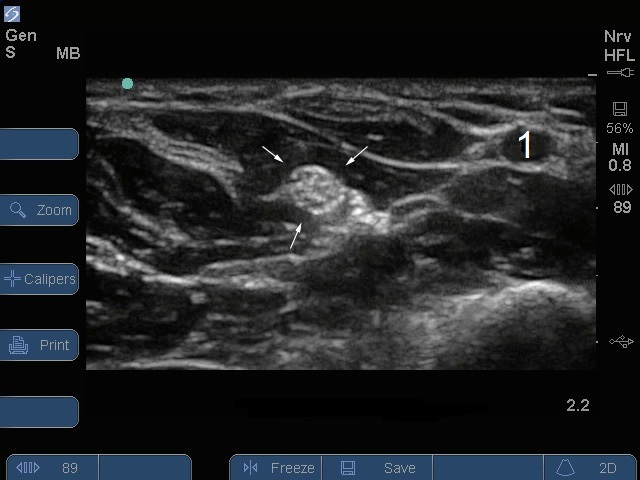

Bild: S Series, Nervus medianus, Unterarm

Pfeile: Nervus medianus

Arterie